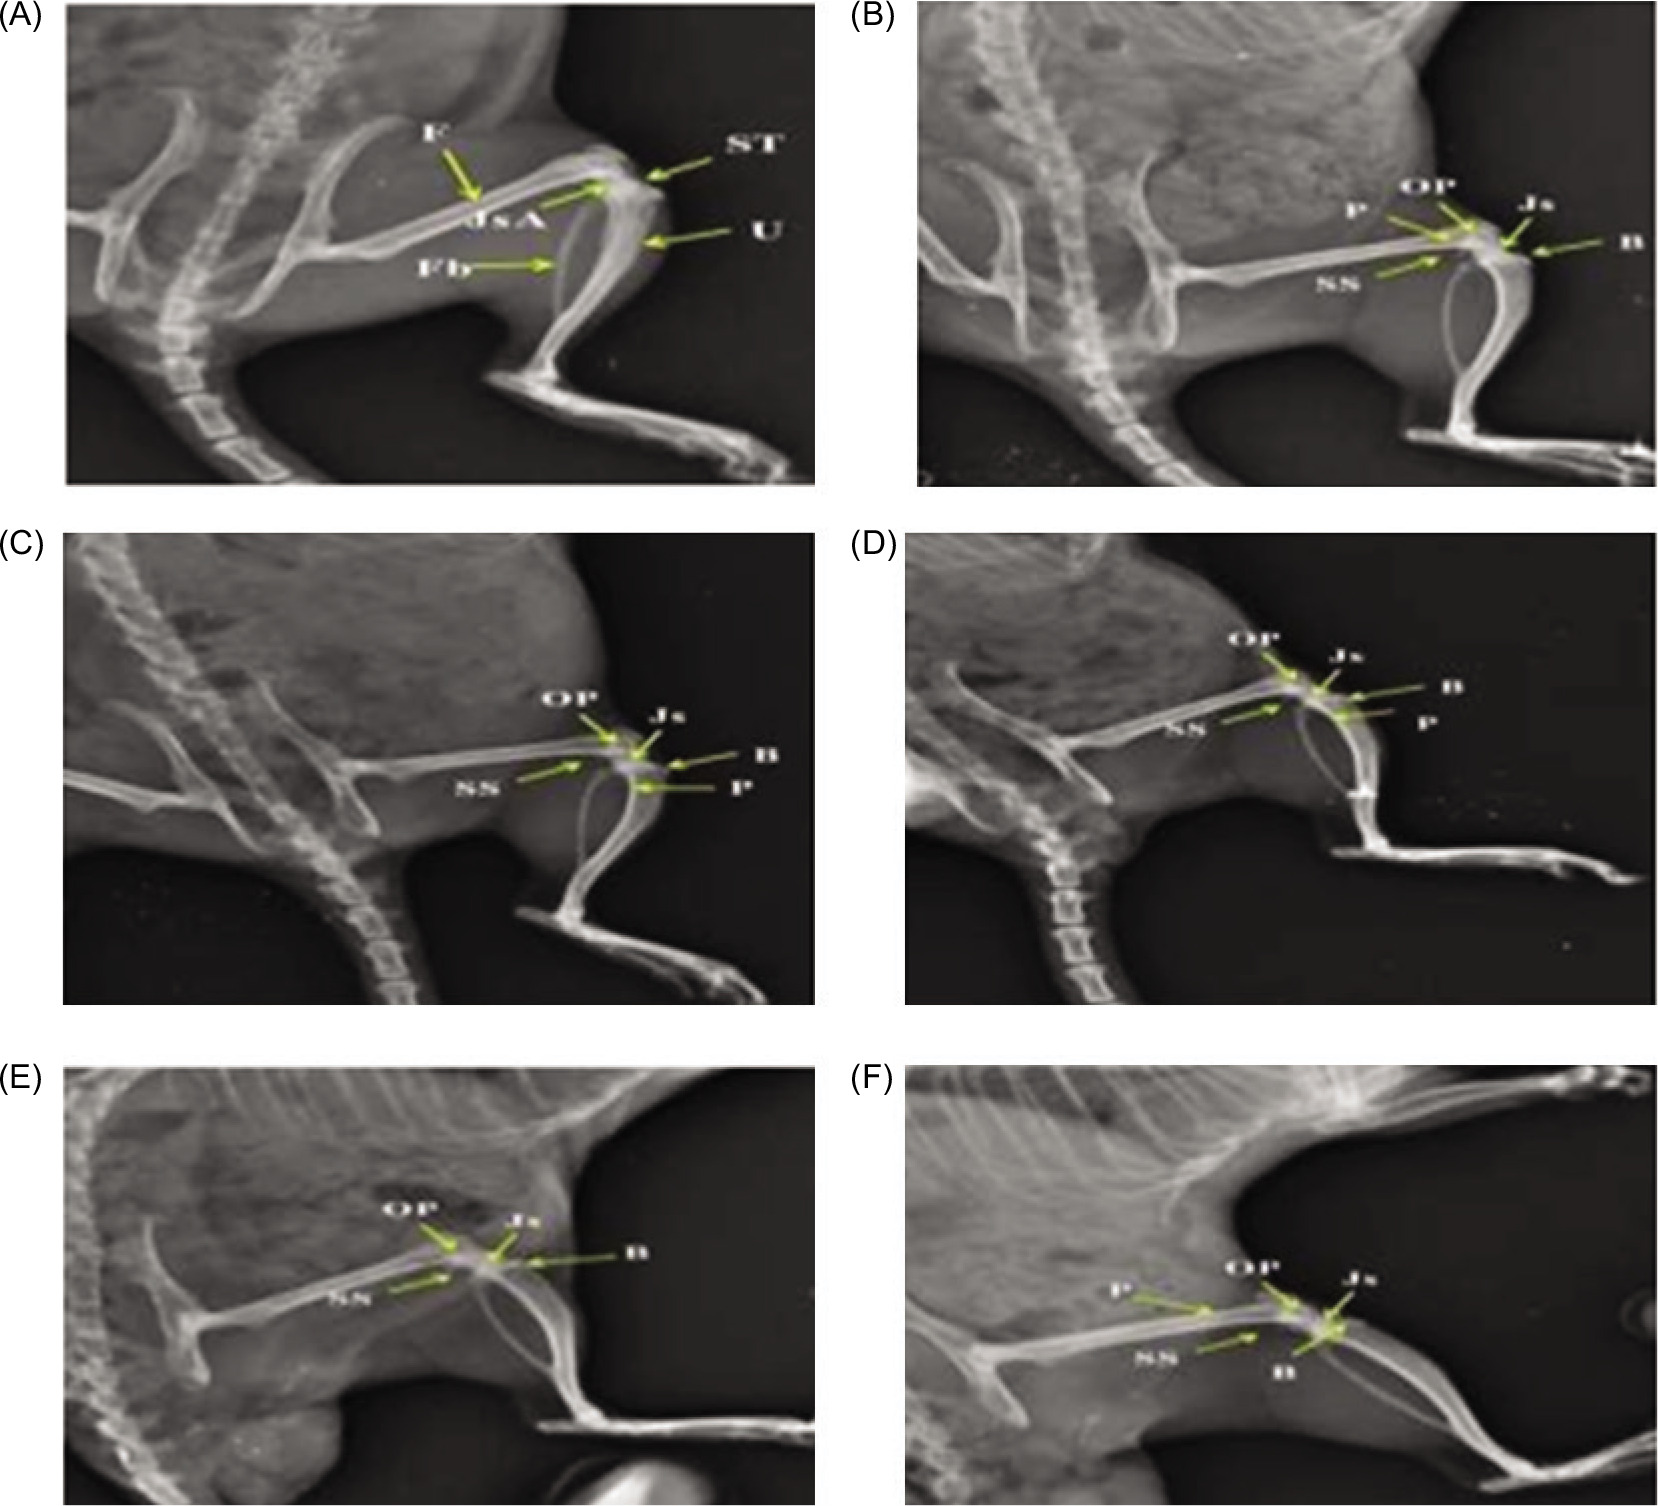

3.5. Radiographic evaluation of knee joints

Radiographs showed intact joints in the normal group, while the disease control group exhibited severe pathology with marked swelling of soft tissues and periosteal reaction (score 3), plus narrowing of joint space and erosion of bone (score 2). Diclofenac significantly improved joint condition with mild swelling and reduced bone damage (score 1). Scitican-50 demonstrated dose-dependent radiological improvements: 50 mg/kg showed moderate pathology, 100 mg/kg reduced periosteal reaction and erosion, and 200 mg/kg provided substantial protection comparable to diclofenac. These findings highlight Scitican’s disease-modifying potential in inflammatory arthritis (Table 3, Figure 2).